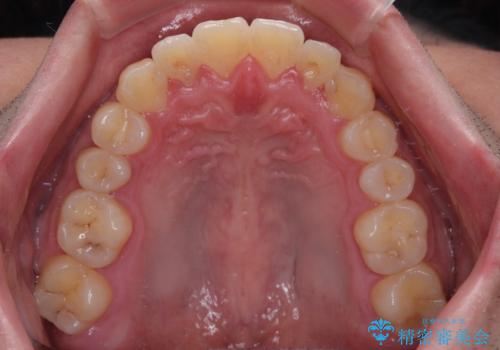

- 八重歯と前歯の隙間を気にして来院された患者様です。

八重歯の改善のため、奥歯を後方に移動させていくこととし、患者様と相談の上、ワイヤー装置にて矯正治療を行うこととしました。

上顎前歯正中の隙間は、舌突出癖によるものと考えられ、舌のトレーニングによる悪習癖改善が必須であるため、徹底するよう指導してから治療を開始することとしました。